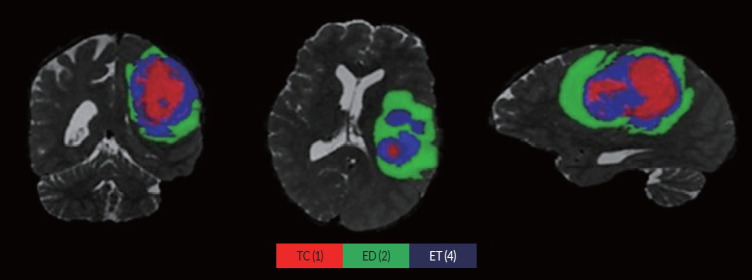

Methods: This study utilizes a support vector machine (SVM) classifier using radiomics features to predict the overall survival (OS) of GBM, IDH-wildtype patients to short (<12 months) and long (≥12 months) survivors. A dataset comprising multi-parametric magnetic resonance imaging scans from 574 patients was analyzed. Radiomic features were extracted from T1, T2, fluid-attenuated inversion recovery, and T1 with gadolinium (T1GD) sequences. Low variance features were removed, and recursive feature elimination was used to select the most informative features. The SVM model was trained using a k-fold cross-validation approach. Furthermore, clinical parameters such as age, gender, and MGMT (O6-methylguanine-DNA methyltransferase) promoter methylation status were integrated to enhance prediction accuracy.

Abstract Image